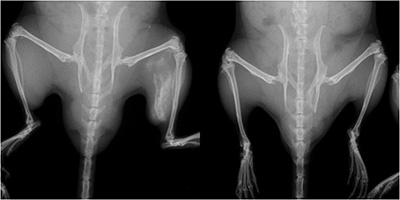

FOP mouse (left) and normal mouse. The FOP mouse shows abnormal bone growth in the left hind leg. CiRA scientists use iPS cells to show that a molecule associated with inflammation could be a therapeutic target for the abnormal bone growth.

For the purpose of FOP drug discovery, scientists have normally focused on molecules associated with BMP signaling. However, CiRA researchers from Professor Junya Tochuchda's lab instead looked at molecules related with inflammation, finding Activin-A as a candidate drug target. "Because patients normally show FOP symptoms after trauma or inflammation, we thought this would be a good strategy," Ikeya said. Using iPS cell technology, the scientists found that only cells harboring the FOP gene mutation would respond to Activin-A by significantly increasing their BMP signaling. Further, transplanting these cells into mice and stimulating them with Activin-A led to abnormal bone.